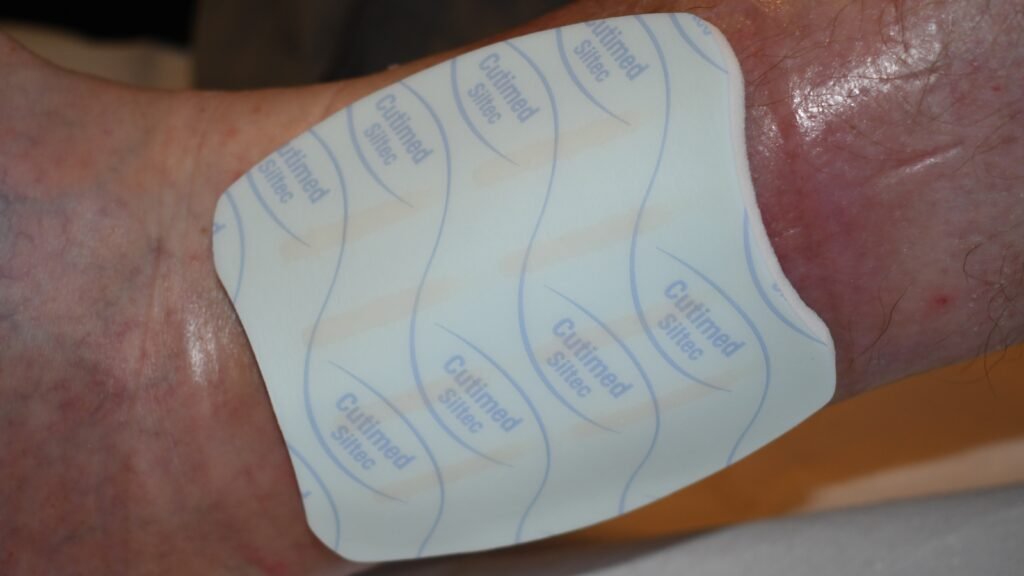

Silikon-Wundauflagen

Zusätzliche – Fotos ![]() 4 Videos

4 Videos ![]() 1

1